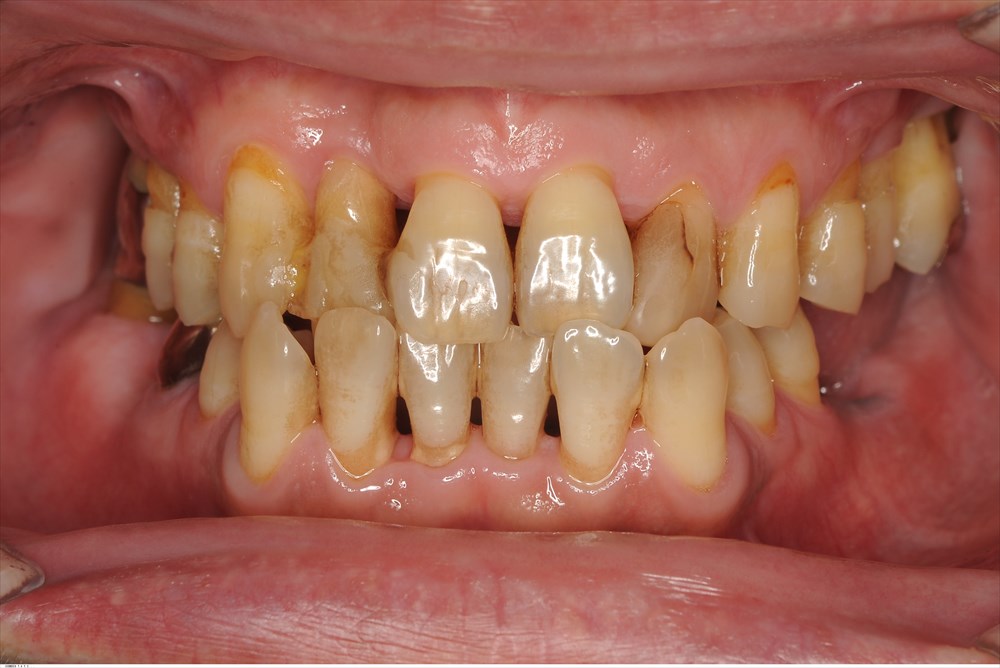

MINST処置後6ヶ月

歯槽骨が明瞭になり安定しています。骨様の再生もありポケットは3mm以下です。